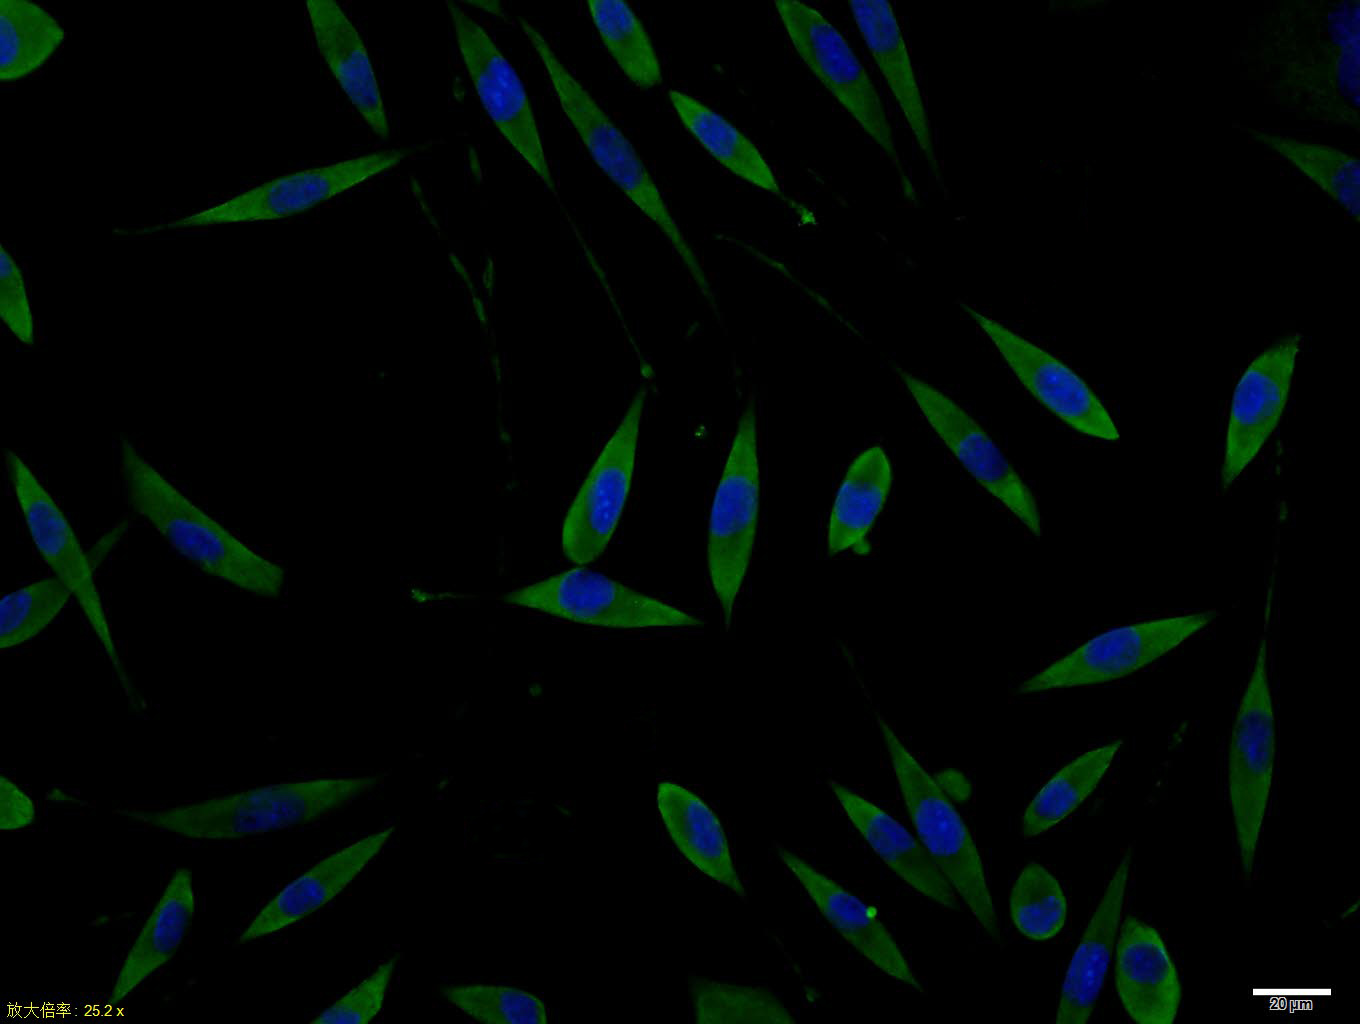

SHSY5Y cell; 4% Paraformaldehyde-fixed; Triton X-100 at room temperature for 20 min; Blocking buffer (normal goat serum, C-0005) at 37°C for 20 min; Antibody incubation with (Phospho-Doublecortin (Ser128)) polyclonal Antibody, Unconjugated (bs-3113R) 1:100, 90 minutes at 37°C; followed by a conjugated Goat Anti-Rabbit IgG antibody at 37°C for 90 minutes, DAPI (blue, C02-04002) was used to stain the cell nuclei.